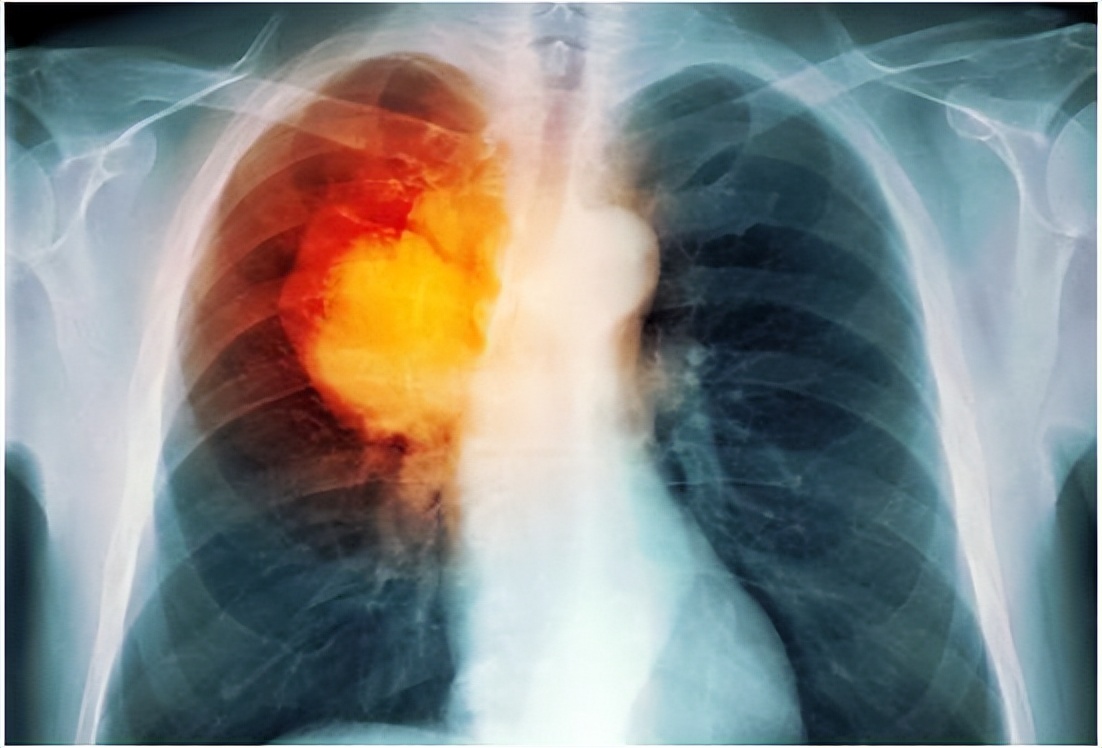

医生解释说,肺是人体重要的器官,人体的肺分为尖、底、体三个部分,它在身体里有举足轻重的作用,因为它的周围遍布着四通八达的神经, 如果靠近此处生长了肿瘤,便容易扩大、病变,导致压迫或侵犯到周围神经,从而导致肩背部疼痛。 这种肺部病变的成因在临床医学上是很常见的。

肩背痛是临床常见的症状,大都为肩背局部骨或软组织疾病所致。在此处发病的几率十分高, 比如人体比较常见的肩周炎、肩关节的骨关节炎、肩袖损伤等。在肩关节处产生炎症往往也会波及到整个肩背部区域,从而引起整个肩背部疼痛,这也是临床大部分人所熟知的。但是很多人并不了解, 其实肩背部的疼痛也可能是肿瘤转移至肩部所致。

大多数人会将肩背部疼痛联想到骨关节、肩关节痛,所以一直采用休息就会好起来的方针,在骨科里治了又治, 最终没有发现肺部的病变。这就导致肿瘤或者病毒已经扩散到了背部、胳膊等地方,等真正查出来的时候,大多数的情况已经十分恶劣了。